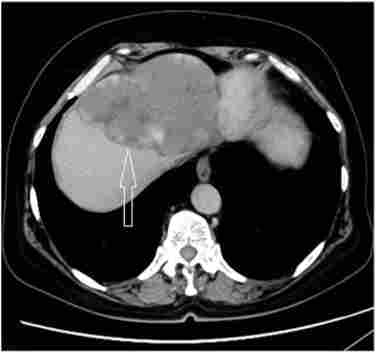

Захворювання виявляється при УЗД печінки, призначеному в якості скринінгу, або при обстеженні з приводу інших причин. При скануванні визначається частіше гіперехогенное новоутворення, відмінне по щільності від паренхіми, або гіпоехогенні без чітких ознак наявності капсули. З огляду на характер васкуляризації пухлини, проведення контрастних методів дослідження - МСКТ / МРТ - дозволяє з імовірністю 90% діагностувати гемангиоматоз і відрізнити його від інших захворювань (аденоми, ГЦК, метастазів і ін.). Відзначається специфічне для гемангіоми нерівномірне накопичення контрастного препарату від периферії до центру (рис. 16.1).

КТ-картина при гемангіома печінки. Візуалізується пухлинний вузол - гемангіома. Пухлина вказана стрілкою

Мал. 16.1. КТ-картина при гемангіома печінки. Візуалізується пухлинний вузол - гемангіома. Пухлина вказана стрілкою